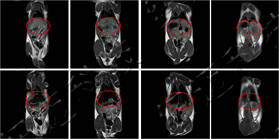

儀器使用小動物核磁共振成像系統(tǒng),圖像為T1加權(quán)像橫斷面、冠狀面,采樣參數(shù)如下:FOV=100mm×100mm, TR=400ms, TE=19ms, 層厚3.5mm, 層間距1mm, 累加次數(shù)16, K空間大小192×256。成像結(jié)果顯示,注射造影劑后,大鼠心臟與肝臟變亮,且隨代謝時間延長逐漸變暗。

大鼠造影前后MRI冠狀面

大鼠體內(nèi)造影劑代謝MRI橫斷面